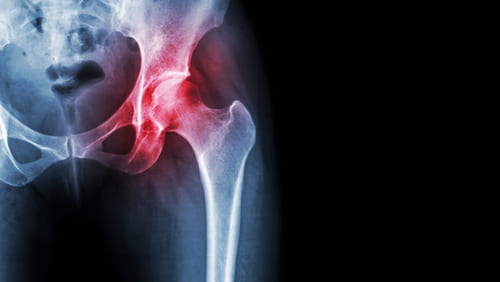

Асептический некроз головки бедренной кости (АНГБК)

Асептический некроз головки бедренной кости (АНГБК) — это хроническая или острая патология дегенеративного характера, при которой наблюдается постепенное отмирание головки бедренной кости человека. Расстройство складывается в довольно позднем возрасте, от 25-30 лет, что отличает эту болезнь от аналогичных. В структуре клиники преобладают болезненные ощущения и нарушения нормальной подвижности. Болезнь складывается остро или формируется исподволь, в течение длительного периода времени, нескольких лет. Пациентам требуется как можно более раннее лечение. Если ничего не делать почти гарантированно разовьется инвалидность разной степени выраженности.

АНГБК развивается в результате нарушения нормального кровообращения в тканях головки тазобедренной кости. Патологический процесс отличается от прочих подобных расстройств, которые преобладают в детские годы. Нарушения локального кровообращения происходят по самым разным причинам. Спусковым механизмом для дистрофического процесса могут стать: